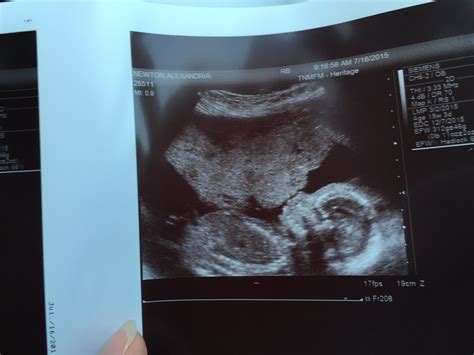

Reaching the halfway mark of your pregnancy is a monumental milestone that often brings a mix of excitement and nervous anticipation. As you settle into your second trimester, you are likely preparing for one of the most significant medical appointments of your entire journey: the 20 weeks pregnant ultrasound. Also known as the anatomy scan or the morphology scan, this comprehensive examination is designed to take a detailed look at your growing baby’s development from head to toe. It is a moment where the reality of parenthood truly begins to sink in as you see your little one’s features, movements, and heartbeat in stunning detail on the screen.

The 20 weeks pregnant ultrasound is a routine diagnostic scan typically performed between 18 and 22 weeks of gestation. Unlike earlier, smaller scans that primarily confirmed the pregnancy and measured the crown-rump length, this appointment is far more thorough. Its primary purpose is to ensure that your baby is developing at a healthy rate and that all major organs and systems are functioning as expected.

The anatomy scan is a transformative moment that bridges the gap between feeling the flutters of movement and seeing the reality of your child. As you view the screen, you might see them yawning, sucking their thumb, or practicing their kicking. These small, fleeting moments are the foundation of your early bond. Once you leave the clinic, you will likely walk away with a set of grainy but precious photos that will serve as the very first addition to your baby’s photo album. Take the time to process this experience, celebrate the health of your baby, and look forward to the remaining months of your journey toward welcoming your little one into the world.